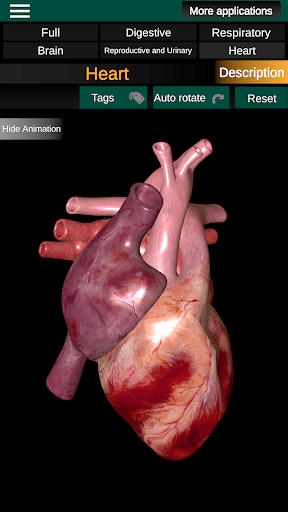

* Hart, dat de atria, ventrikels, aorta en een animatie van dit orgel omvat.

* Gemakkelijk te openen en te navigeren (zoom, 3D-rotatie).

* Beschrijvingen van elk orgel.